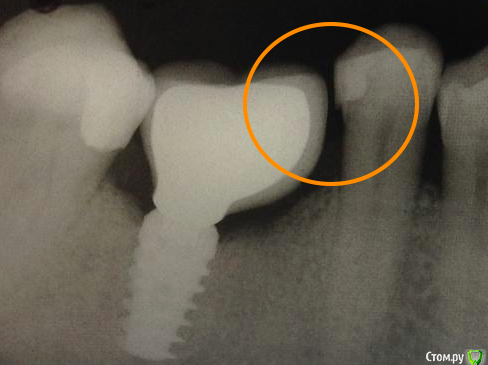

drvikont Опубликовано 14 марта, 2016 Поделиться Опубликовано 14 марта, 2016 а что с контактным пунктом?он вовсе отсутсвует Ссылка на комментарий

Shakirbura Опубликовано 14 марта, 2016 Автор Поделиться Опубликовано 14 марта, 2016 а что с контактным пунктом?он вовсе отсутсвуетКоллега, я же в посте написал, что исправлен пункт) Ссылка на комментарий

Борис80 Опубликовано 14 марта, 2016 Поделиться Опубликовано 14 марта, 2016 Я бы порекомендовал обращать внимание на наклон зубов пациента , ограничивающих дефект... они очень часто наклонены в сторону имплантата и качественный контактный пункт не получается... Ссылка на комментарий